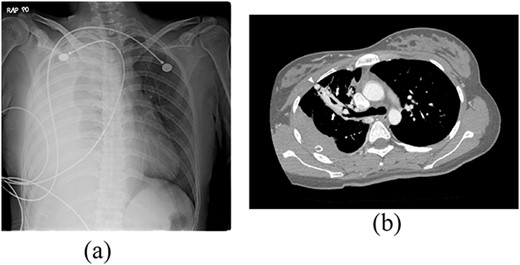

A 24-year-old female in the 21st week of pregnancy was transferred to the emergency department. Twelve hours before admission, the patient developed a tearing pain from the back to the right chest and dyspnea. There was no relevant medical history. Vital signs were systolic blood pressure of 83 mmHg, diastolic blood pressure of 58 mmHg, and pulse rate of 142/min. Initial hemoglobin level was 8.9 g/dl with a platelet count of 99 000/μl. Chest radiographs revealed a massive right pleural effusion with a mediastinal left shift (Fig. 1a). A closed thoracostomy was performed, and 2 l of blood was drained from the pleural cavity. Contrast-enhanced chest computed tomographic scan revealed a potentially ruptured PAVM in the anterior segment of the right upper lung (Fig. 1b). The patient was transfused with five packs of red blood cells and two packs of frozen fresh plasma. Emergency video-assisted thoracoscopic surgery (VATS) was performed. A 5-cm-sized working widow was created in the fifth intercostal space mid-axillary line. Two additional 10.5-mm ports were inserted in the sixth and seventh intercostal spaces in the anterior and posterior axillary lines. A half-liter of blood clots were removed. The PAVM, active bleeding on soft palpation, was visible on the right upper lung surface and was resected with two endostaples (Fig. 2). The patient developed disseminated intravascular coagulation and acute kidney injury postoperatively and was managed in the intensive care unit (ICU) for 3 days. She was recovered and was discharged 6 days after the operation without residual complications. The fetus had no particular problems related to the operation. However, it was miscarried after hydrocephalus and pericardial effusion were discovered. A follow-up computed tomographic scan 8 months after the operation revealed no residual PAVM (Fig. 3).

Radiograph of a 24-year-old woman with chest pain and dyspnea. (a) Chest radiograph showing right massive effusion causing left shifting of the mediastinum. (b) Enhanced axial CT showing the direct connection of a branch of the anterior segmental pulmonary artery (down arrow) with a vein (up arrow) and dilated vessel on the surface of the anterior segment of the right upper lung (arrowhead).